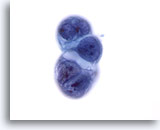

画像 2: 肝FNA – 良性肝細胞

反応性変化を来した良性肝細胞の集塊。細胞境界が明瞭な立方形の細胞が認められます。不透明な細胞質には空胞が認められるものもあれば、幾分顆粒状を呈するものもみられます。辺縁部は擦り切れた状態を呈しています。核はわずかに大小不同で、二核を有する細胞も認められます。小型の核小体がみられます。

40倍

画像 2

肝FNA – 良性肝細胞

反応性変化を来した良性肝細胞の集塊。細胞境界が明瞭な立方形の細胞が認められます。不透明な細胞質には空胞が認められるものもあれば、幾分顆粒状を呈するものもみられます。辺縁部は擦り切れた状態を呈しています。核はわずかに大小不同で、二核を有する細胞も認められます。小型の核小体がみられます。

40倍